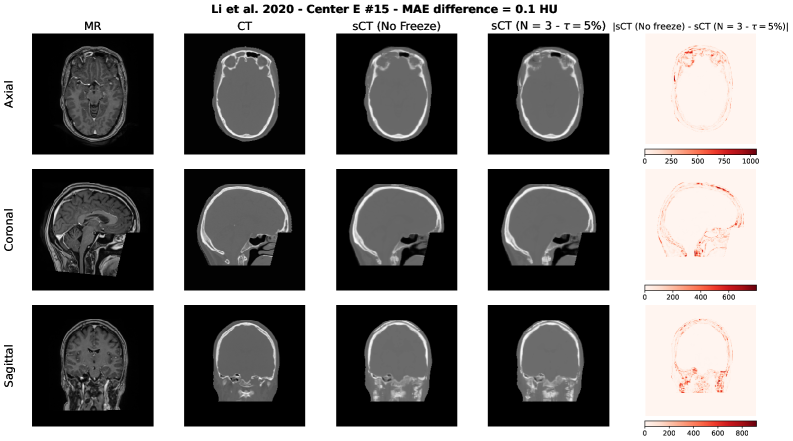

To qualitatively assess the potential impact of the adaptive freezing strategy on the generated synthetic CTs (sCTs), we conducted a visual comparison between the sCTs obtained with and without the proposed methodology. For each model employed in the study, we selected two representative test cases based on the following criteria:

• The case with the minimum difference in terms of MAE, thus the lowest difference between the sCTs MAE generated with and without adaptive freezing.

• The case with the maximum difference in terms of MAE, thus the highest difference between the sCTs MAE generated with and without adaptive freezing.

Each figure presents the following for the axial, coronal and sagittal plane of the central slice:

1. 1.

Input MR image;

2. 2.

Ground-truth CT image;

3. 3.

sCT generated without adaptive freezing;

4. 4.

sCT generated with the proposed adaptive freezing, using 𝒩=3\mathcal{N}=3 and τ=5%\tau=5\%;

5. 5.

Absolute difference map between the two sCTs.

Figure S3: Li et al. architecture [36] – Minimum MAE difference case.

Refer to caption

Across all models and both selected cases, no relevant and systematic structural differences were observed. The differences highlighted in the absolute difference maps and the variation in MAE are attributable to the stochastic nature of the training process (e.g., batch shuffling and optimization path variability) rather than the direct effect of the adaptive freezing mechanism.

This findings are aligned with the results observed in terms of MAE, PSNR and SSIM presented in this study.